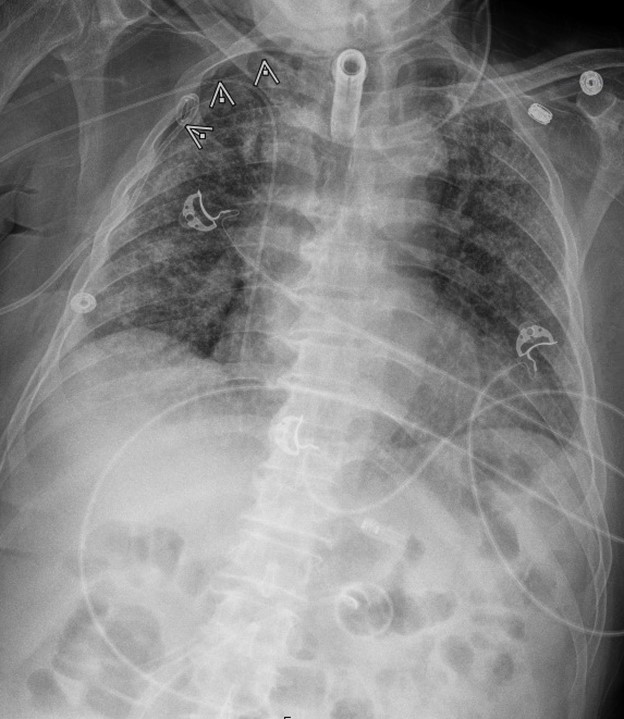

Target directed pain management therapies to the causal nerve, bone, or tendon provide a unique way to provide analgesia while decreasing the need for opiate consumption. The Serratus Anterior Plane Block (SAPB) is a commonly used regional block that was developed as a safer alternative to the thoracic paravertebral and neuro-axial thoracic epidural.3 It provides hemi-thoracic analgesia by blocking the thoracodorsal, long-thoracic, and intercostal nerves from T2-T9. Herein, we describe the use of a SAPB for non-emergent thoracostomy for the treatment of a spontaneous pneumothorax. The patient was a 62 year old male who presented to the ED with worsening dyspnea and was found to have a moderate-sized right-sided spontaneous pneumothorax without midline shift. The decision was made to pursue the placement of a pig-tail catheter and admit for observation. Prior to pig-tail placement, a SAPB was performed to optimize intra-procedure and postoperative pain control. The SAP block was performed by placing a linear transducer in the coronal plane in the mid-axillary line, starting at the clavicle and moving caudal to the fourth rib space, wherein the serratus anterior can be identified superficial to the ribs and deep to the latissimus dorsi. A mixture of 15 mls of Bupivacaine 0.5% and 15 mls of saline for a total volume of 30 cc was injected into the fascial plane located between the serratus anterior and latissimus dorsi. This was well below the toxic dose of 2-2.5mg/kg.4 The patient developed analgesia extending from approximately T2/T3 to T8, and the patient tolerated pigtail catheter placement at the fourth intercostal space. The patient required no additional pain medication after the initial placement and had good pain control after being evaluated two hours and six hours after the block was completed. The chest x-ray is provided below.